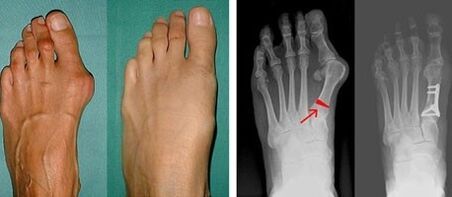

Behatz lodiaren eta behatz txikiaren valgus identifikatzearen lehen fasean, medikuak ikusmen-azterketa bat egiten du. Modu honetan, patologiaren garapen-etapa zehazten du. Artikulazioetan aldaketa zehatzak identifikatzeko, X izpiak eta plantografia agintzen dira.

Ikusmen-azterketak eta X izpiek emaitzarik ematen ez badute, pazientea plantografiara bideratzen da, oin lauak posibleak zehazteko. Metodo honek oinen estanpatuak hartzen ditu, eta horren arabera egiten zaizkio pazienteari propietate ortopedikoak dituzten oinetakoak edo barne-zolak. Ondoren, pazienteari podometria agintzen zaio. Metodo honek ordenagailuaren analisia erabiltzen du pertsona batek oinetan duen pisuaren presioa zehazteko. Diagnostiko aurreratuen emaitzak lehen eta bigarren behatzaren makurdurarako tratamendu metodo bat aukeratzeko oinarria dira.